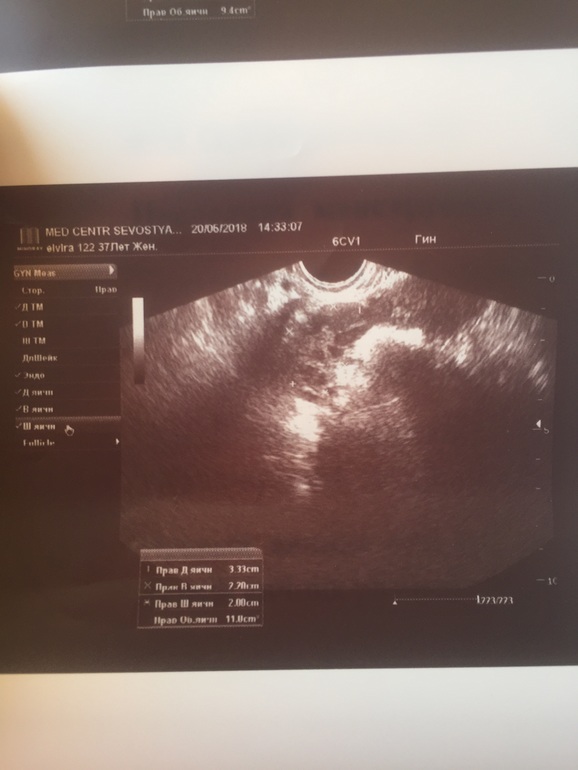

Здравствуйте,вчера была на УЗИ,болит то справа то слево в области яичников отдаёт иногда в ногу и спину.

Врач УЗИ говорит все чисто матка хорошая,шейка и придатки хорошие чистые.

Есть свободная жидкость в малом количестве,спросила значит прошла овуляция,она говорит наверное...

После говорит что не видит доминантного фолликула и вообще говорит что яичники похожи на поликизтозные,хотя я у прошлом месяце была на УЗИ все было хорошо и фолликул был и жёлтое тело помогите разобраться фот снимки УЗИ